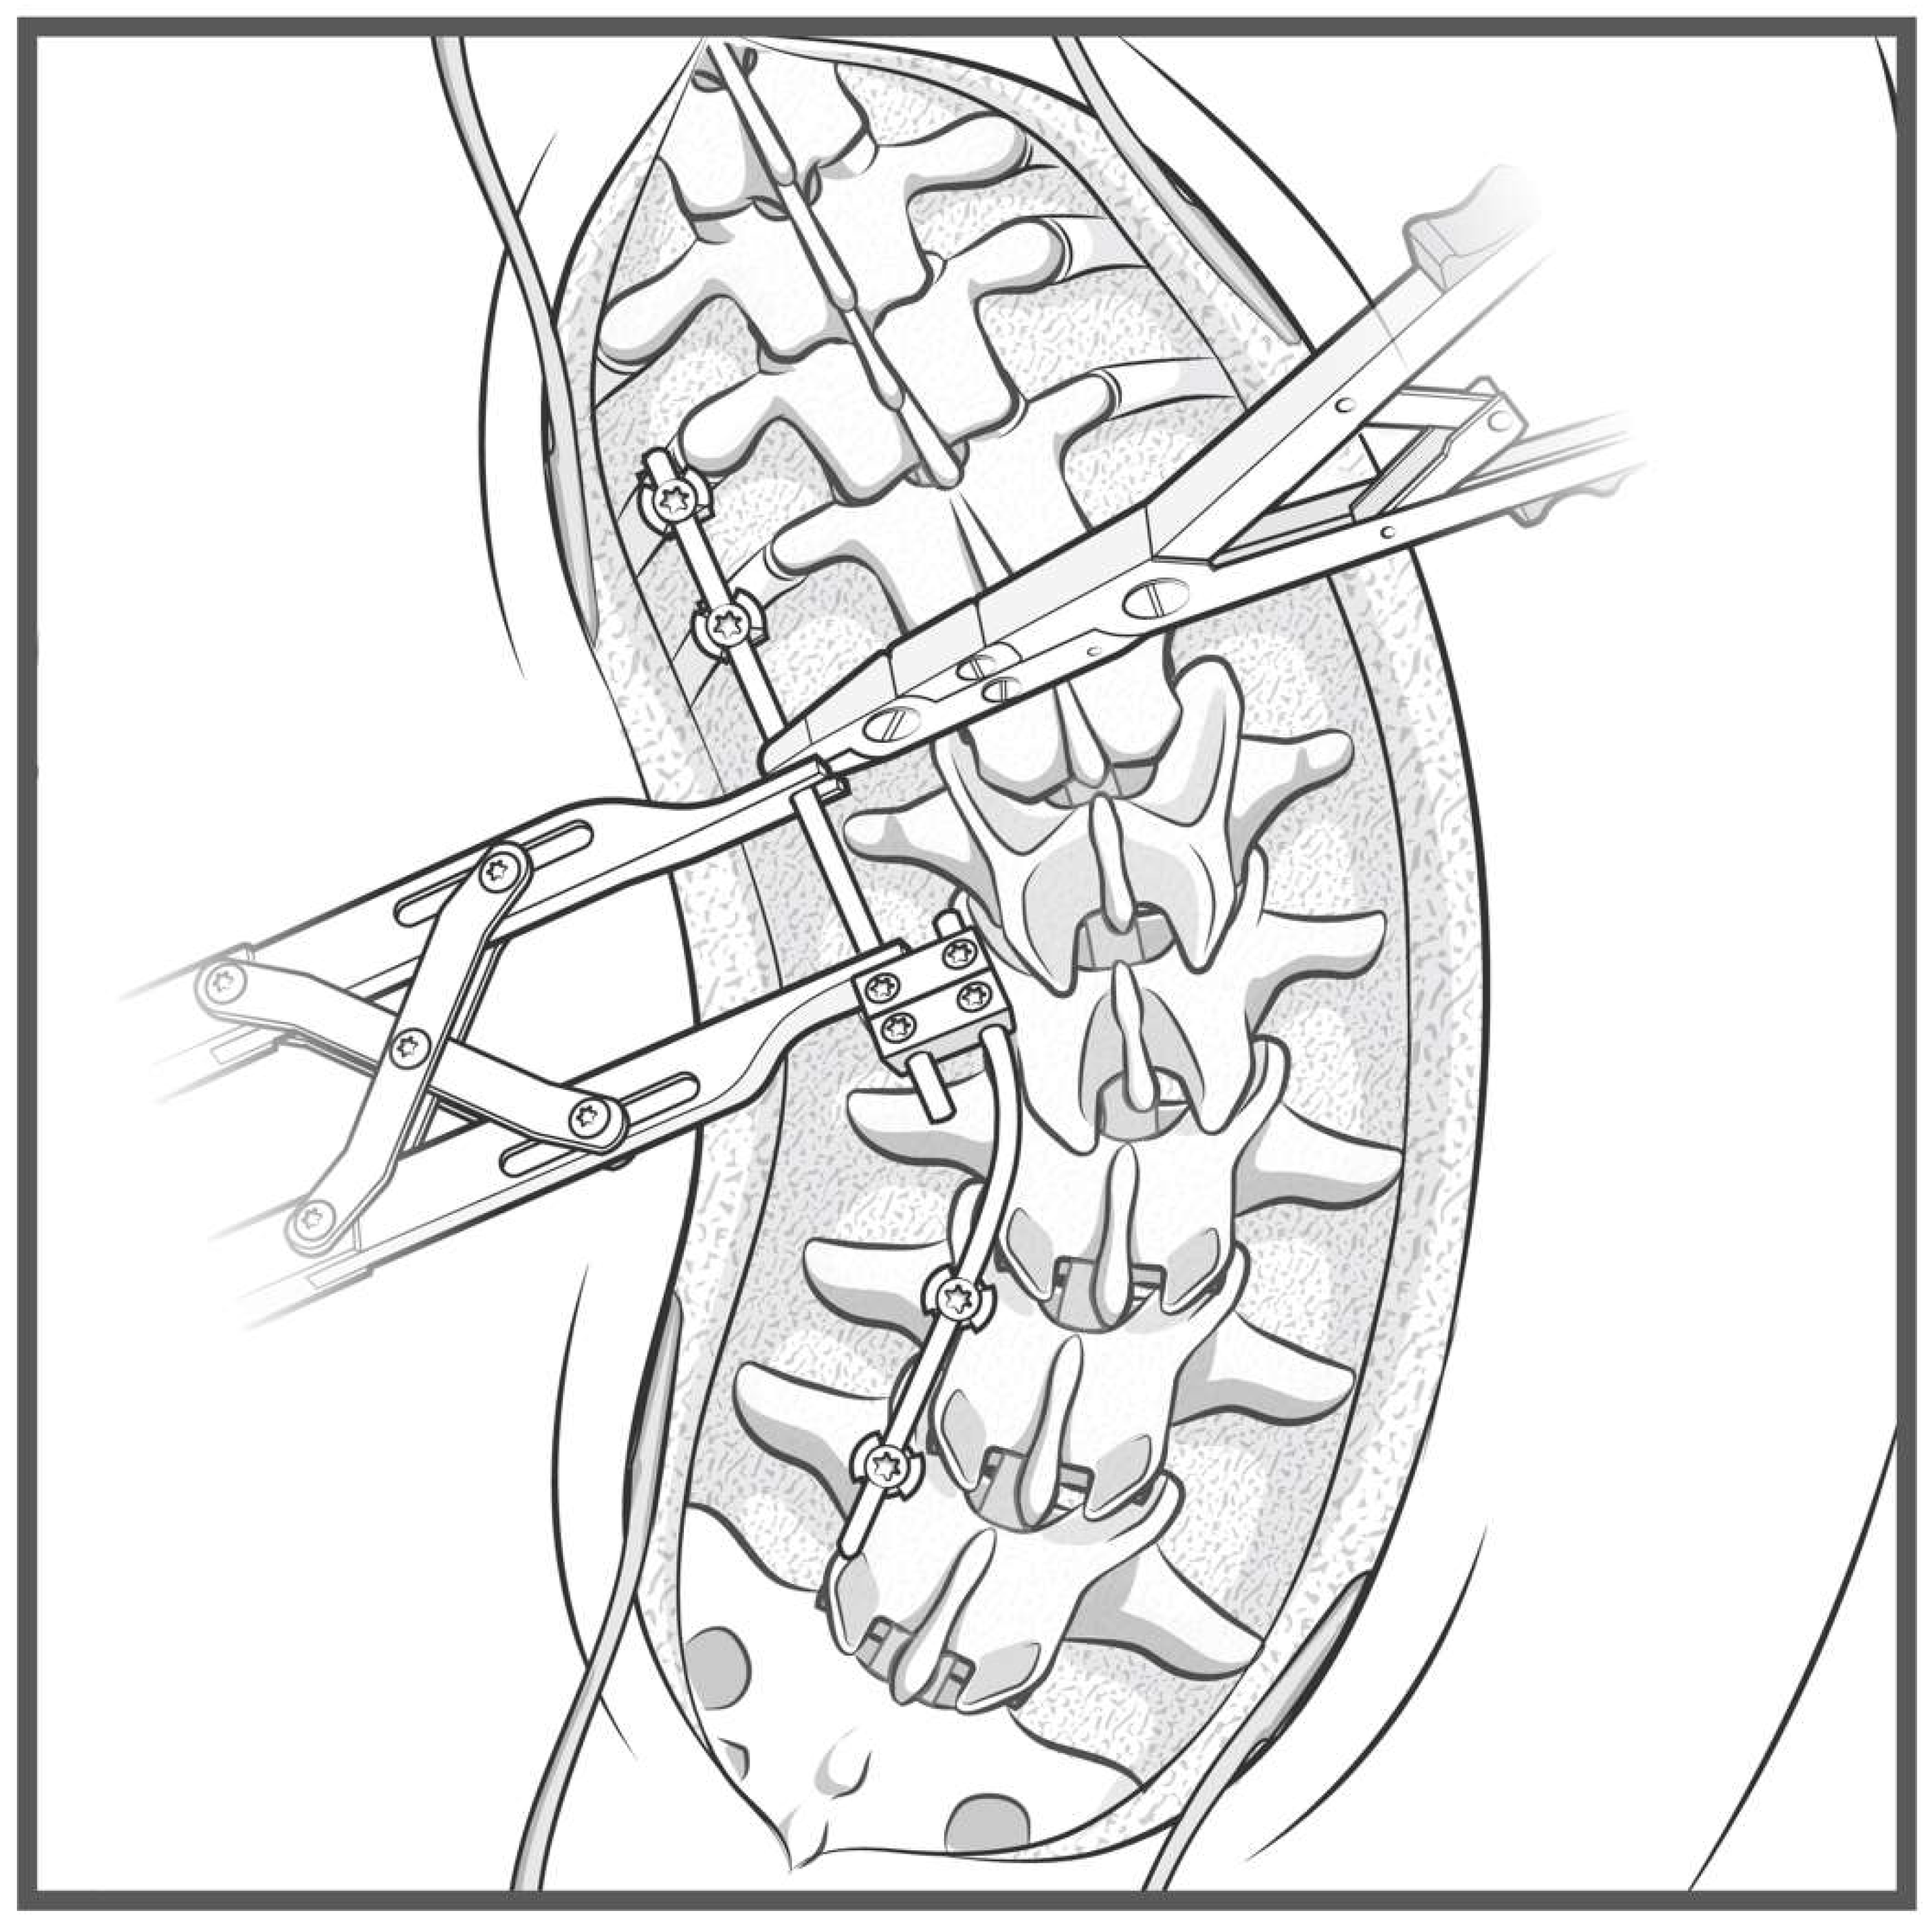

A detailed surgical technique guide by Buchowski et al. in 2007 describes temporary internal distraction in a broader context and highlights important considerations, such as preoperative surgical planning, patient positioning, and placement of proximal and distal anchor points [4]. However, this report aims to focus on the placement and configuration of spinal rods for internal distraction or compression utilizing the construct-to-construct technique. To set up the construct-to-construct configuration, one rod is attached to the proximal anchor points and a second rod to the distal anchor points. There should be at least two (or more) anchor points at the proximal and distal ends to set up this technique. This helps prevent plowing of pedicle screws by distributing the distractive and compressive forces across several motion segments along the spine. These rods are joined by one or two lateral domino connectors to complete the construct-to-construct setup. The more overlap of the rods, the more “runway” there is to apply distraction (Figure 1). Conversely, the less overlap that exists between these two rods, the more “runway” there will be to apply compression (Figure 2). If internal distraction is desired, this construct-to-construct configuration will need to be set up on the concavity of the scoliosis curve. Alternatively, the construct-to-construct configuration will need to be set up on the convexity of the scoliosis curve if internal compression is needed. Distraction or compression is then applied to these rods in a serial, “click-by-click” fashion after loosening the ipsilateral set caps on the domino connectors. Rod grippers may be used to distract or compress against instead of utilizing pedicle screw tulips in order to reduce loosening of the anchor points. After the desired amount of deformity correction is achieved, the set caps on the domino connectors are tightened to hold the correction.

Figure 3. Step-by-step schematic of the construct-to-construct internal distraction technique. The green caps represent loose set caps. Red caps represent tight set caps.